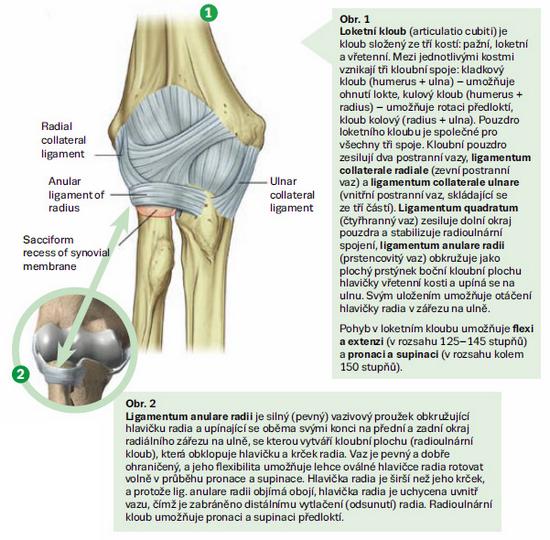

Pronatio dolorosa (lat. bolestivá pronace, Chassaignacova obrna) je bolestivé držení lokte u malých dětí, vzniklé po prudkém tahu a rotaci ruky, při kterém dochází k subluxaci hlavičky radia v lokti s uskřinutím lig. anulare. Nejčastěji vzniká u dětí mezi 2. a 4. rokem při tahu za zápěstí či předloktí např. vytahováním dítěte za jednu horní končetinu vzhůru, zejm. při zabránění pádu. Patří k nejčastějším úrazům malých dětí.

Pronatio dolorosa je méně závažné, ale časté poranění, které vzniká při násilném tahu za pronované a hyperextendované předloktí, kdy ligamentum anulare radii (vřetenní prstencový vaz) sklouzne přes hlavičku radia a uskřine se mezi hlavičku radia a capitulum humeri (do radiohumerálního kloubu). Vzniká nejčastěji tak, že dítě vedené za ruku padá a rodič ve snaze zabránit pádu ho prudce zatáhne za ruku. Tělo dítěte rotuje kolem ruky a působí celou vahou na loketní kloub. Dále může vzniknout při manipulaci s nespolupracujícím dítětem či při hře, kdy starší kamarád nebo člen rodiny točí (pohupuje) dítětem za jeho ruce či předloktí.

Vazy malých dětí ještě nejsou plně vyvinuty, proto i malá síla působící na kloub může způsobit jeho posunutí nebo částečné vykloubení. Částečně je to dáno i mechanismem poranění, který staví tuto věkovou skupinu do rizikové skupiny – batolata často chodí ruku v ruce s vyšším dospělým či starším dítětem. Je zde ale i anatomická predispozice k subluxaci hlavičky radia u dětí mladších šesti let. Jak děti rostou, jejich kosti se postupně zpevňují a vazy sílí, což pomáhá udržet loket pevně v místě, a proto je riziko subluxace hlavičky radia u dětí starších pěti či šesti let méně pravděpodobné. Dívky jsou více ohroženy než chlapci, a rovněž levá paže bývá častěji postižena (pravděpodobně z toho důvodu, že většina rodičů jsou praváci, a tudíž drží dítě za levou ruku). Měkké tkáně nebývají postiženy. Ligamentum anulare radii může být u některých malých dětí obzvlášť uvolněné, což může vést k opakovaným subluxacím hlavičky radia. Subluxace hlavičky radia je jen zřídka způsobena pádem (při něm hrozí spíše zlomeniny). Tento úraz je vzácný v mladším dospělém věku.